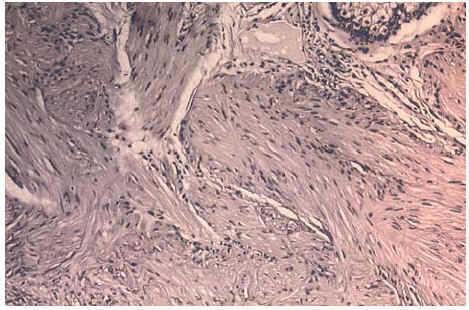

Un varón de 70 años de edad, sin antecedentes patológicos de interés, consultó por presentar lesiones cutáneas en hemicara y costado izquierdo desde los 25 años de edad. Inicialmente estas lesiones eran asintomáticas, pero actualmente se acompañaban de un intenso dolor durante los meses de invierno, con el mínimo roce, y también de forma muy llamativa presentaba crisis de dolor paroxístico durante el sueño, especialmente si éste se acompañaba de pesadillas, ocasionándole constantes despertares nocturnos. La exploración física reveló una placa compuesta por lesiones papulonodulares de color eritematovioláceo, dolorosa a la palpación y de consistencia firme, localizada en la región mandibular izquierda (fig. 1). Se observaron también numerosas lesiones papulosas de diámetro inferior a 1 cm, unas de coloración marrón claro y otras de color de la piel adyacente, con superficie lisa y bien circunscritas, localizadas en brazo y en costado izquierdo, afectando tanto a su cara anterior como posterior, donde varias de estas lesiones se agrupaban siguiendo una disposición segmentaria. Al interrogatorio realizado el paciente refería varios miembros de su familia afectados con las mismas lesiones, en concreto su abuelo paterno, su padre y una hermana, en la que coexistían además leiomiomas uterinos. Se confirmó el diagnóstico de leiomiomas cutáneos múltiples unilaterales familiares mediante exéresis-biopsia de una de las lesiones (fig. 2). Los estudios complementarios realizados (analítica completa de sangre y orina, proteinograma y radiografía de tórax) no detectaron anomalías. Dada la intensa sintomatología que presentaba el paciente, y la limitación del tratamiento quirúrgico para extirpar todas las lesiones dolorosas, se decidió realizar tratamiento médico con gabapentina. Las dosis iniciales fueron de 300 mg al día, ascendiendo progresivamente hasta alcanzar la dosis diaria de 900 mg. A las 2 semanas del iniciarse el tratamiento el paciente refería una importante disminución del dolor, de las molestias subjetivas que le ocasionaban las lesiones e incluso una disminución del tamaño de las mismas que no fue comprobado clínicamente. El paciente no presentó efectos secundarios y actualmente está con dosis de mantenimiento de 900 mg/día, realizando controles periódicos sin recidiva de su sintomatología.

Fig. 1.--Lesión de la región mandibular izquierda consistente en una placa compuesta por numerosas lesiones papulonodulares de color eritematovioláceo.